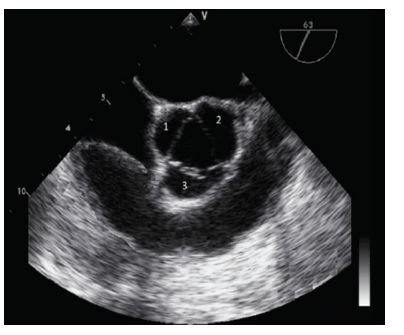

Na imagem abaixo, a estrutura correspondente ao número...

Na imagem abaixo, a estrutura correspondente ao número 1 é: